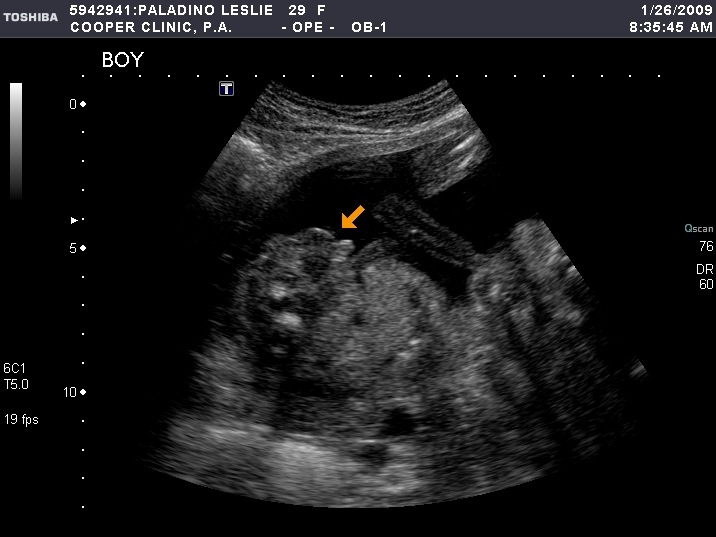

The money shot.  The arrow is pointing at the confirmation that it's a boy, just in case you can't tell.I20090126083752578